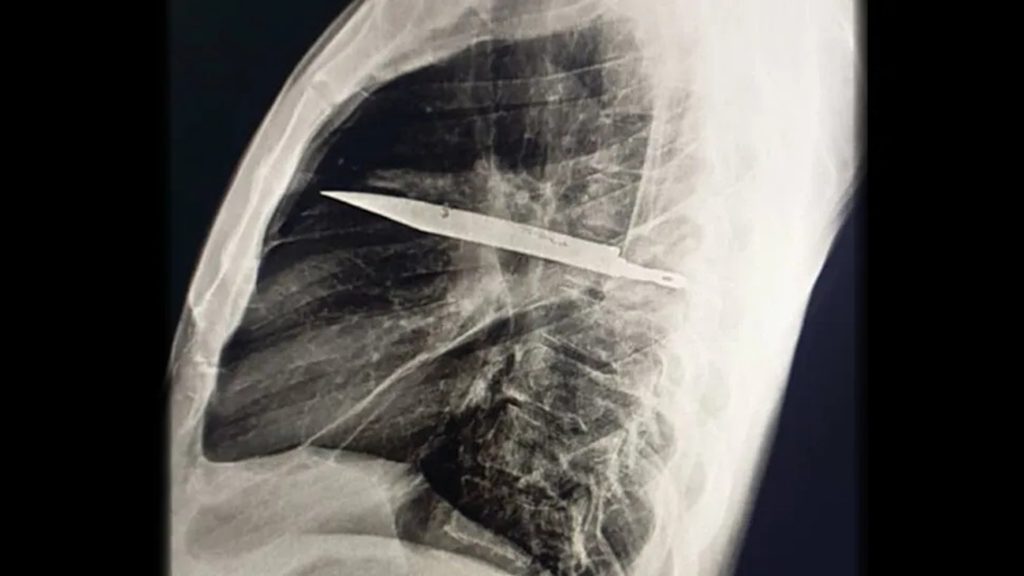

Az elképzelhetetlen helyzet arra figyelmeztet, hogy az immunrendszer képes megvédeni a testet az idegen tárgyaktól. A kés beágyazódása körül kollagénnel és egyéb rostokkal burkolta be a seb, módosítva ezzel a szövetek károsodását, amit az évek alatt senki nem vett észre. A CT-vizsgálat során megdöbbentő képek kerültek napvilágra; a penge egészen a bordák hátsó részétől a jobb lapockáig juttatott a mellkas mélyébe, elkerülve a létfontosságú tüdeket.

A sebészek a műtét során a mellkast átmetszve távolították el a késet, először lecsapolták a felgyülemlett gennyet, majd átmosták a mellüreget, végül behelyezték a szükséges csöveket. Az operáció után a férfi gyorsan felépült, és a megfigyelési időszakot követően elhagyhatta a kórházat.